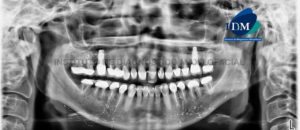

Paciente de sexo femenino de 45 años de edad acude al Instituto de Diagnóstico Maxilofacial para evaluación imagenológica integral. A la evaluación de la radiografía